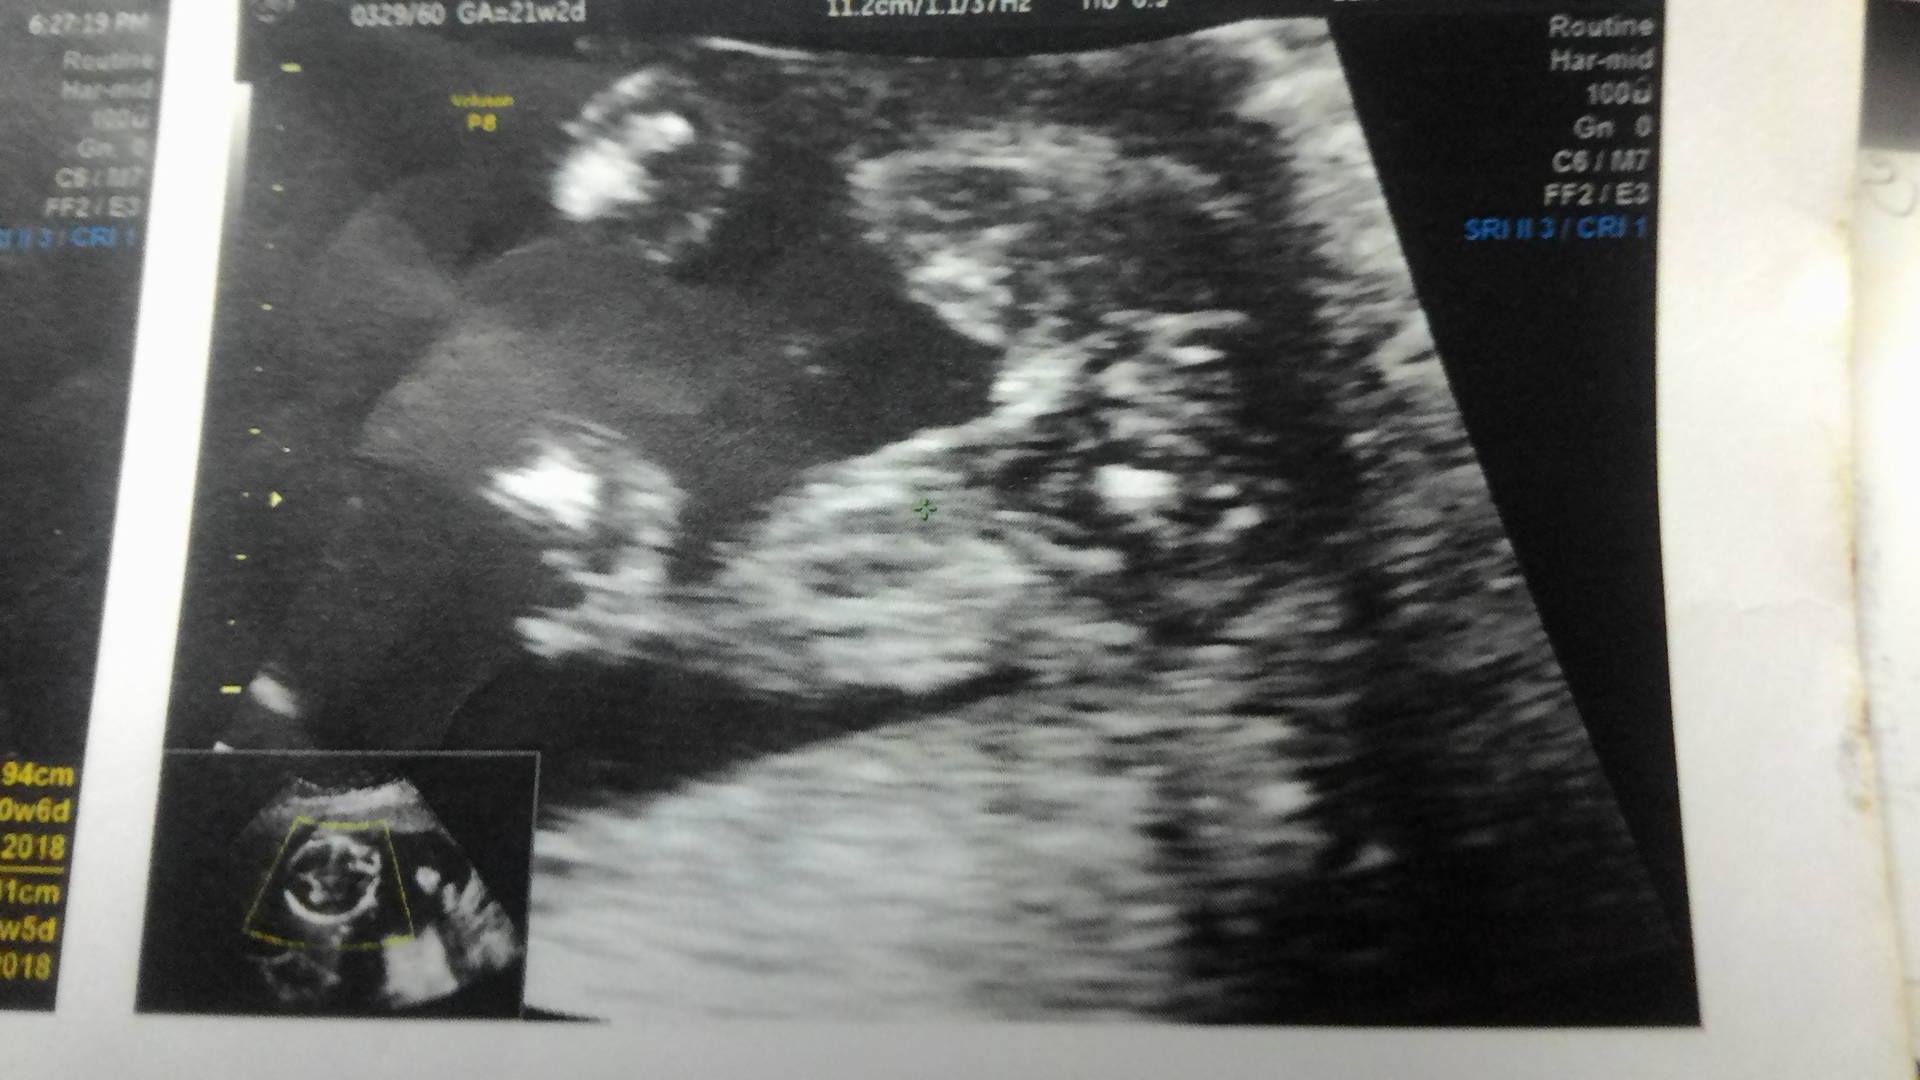

ช่วยดูภาพอัลตร้าซาวด์หน่อยค่ะ ได้ผู้หญิงหรือชาย

รบกวนช่วยดูภาพอัลตร้าซาวด์หน่อยค่ะ เป็น หญิง หรือ ชาย ไปซาวด์ช่วงอายุครรภ์ 20 สัปดาห์ คุณหมอบอกว่า น่าจะ ผู้หญิง แต่ 50 % เพราะน้องหนีบขาไว้แล้วก็มีสายรกอยู่ตรงกลางค่ะ ตอนนี้ 28 สัปดาห์แล้วค่ะ ยังไม่ได้ซื้อของเตรียมเลย